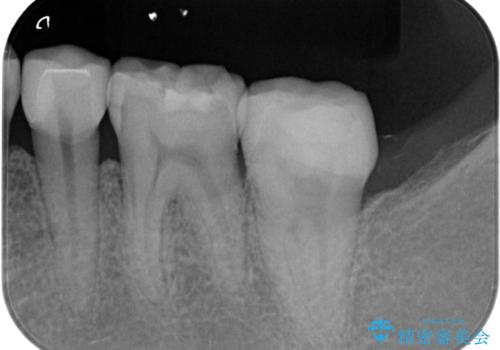

- 出産して落ち着いたから虫歯のチェックをしてほしいとのことで来院されました。

左下の奥歯に詰まっている樹脂の周辺が虫歯になっていたため、治療を進めていくこととなしました。

- 左下7 仮歯+e-maxクラウン:11,000円+77,000円費用は治療当時の料金となります

今回の場合、虫歯の大きさが大きく本来であれば歯茎に対しても治療をすることが検討されケースですが、ご希望されなかったため被せ物のみでの治療となりました。